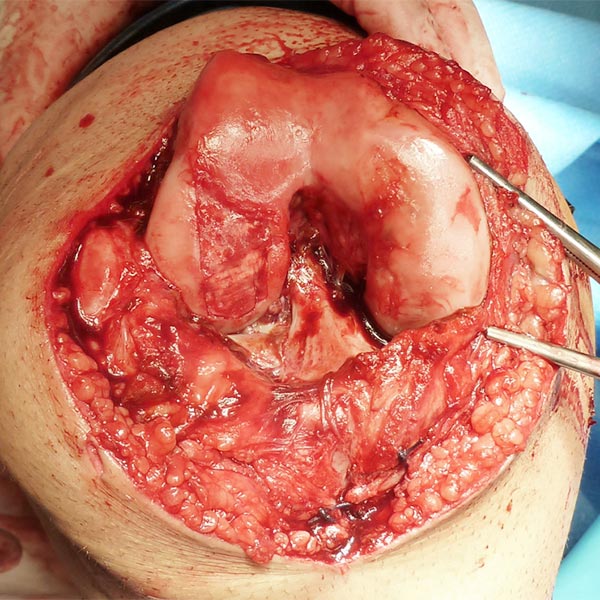

Intraoperatives Bild nach Eröffnung des Kniegelenks. Die Synovia ist durch die wiederkehrenden Entzündungsvorgänge der Thrombophlebitiden stark hyperplastisch und von venöser Malformation durchsetzt. Durch diese Blutfüllung wirkt sie dunkel verfärbt. Gerade noch sichtbar auch ein Teil des Knorpeldefekts.